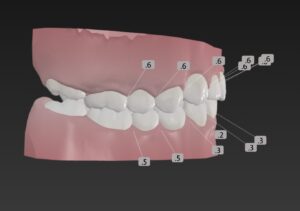

でっ歯さんを治すのに

小臼歯は非抜歯で計画

この歯並びが治る原理はⅡ級ゴムで

上の歯列を後ろに引っ込める

えんしん移動を行う

そうせい

歯と歯の間を少し削りスキマを作って

これを利用し歯をキレイに整列